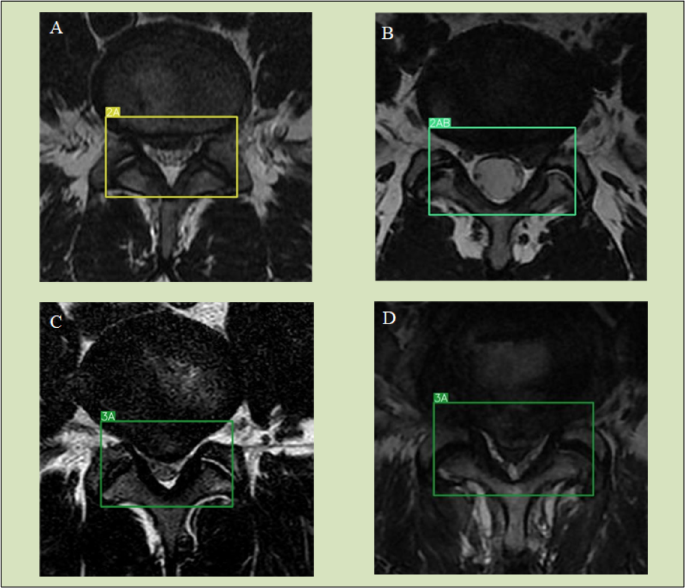

Case illustration

The model’s diagnostic and treatment recommendations in representative L4–L5 disc herniations through axial MRI analysis (Fig. 5): Panels A and B: Axial T2-weighted MRI showing > 50% posterior disc displacement into the central canal (Zone A) and lateral recesses (Zone B), classified as MSU Grade 2 A and 2AB. Panels C and D: Transligamentous extrusion beyond interfacetal margins (> 100% displacement), classified as MSU Grade 3 A.

Demonstrates diagnostic of representative L4-L5 disc herniation through axial MRI analysis. (A) (2 A) and (B) (2AB) demonstrate disc material extending > 50% beyond the interfacetal line. (C,D) (3 A) illustrate the model’s precise detection of transligamentous extrusion beyond the interfacetal margins.